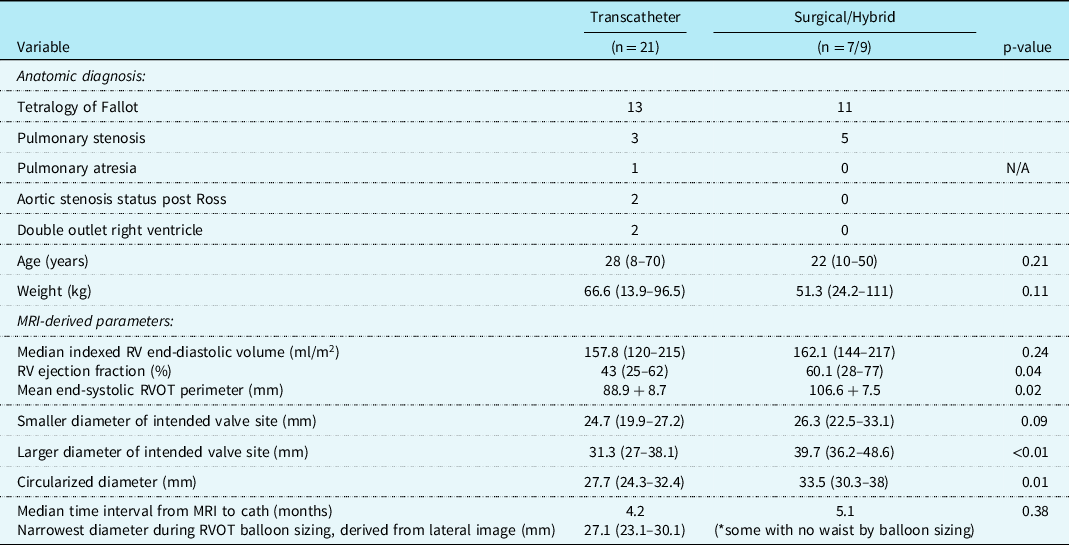

Table 1. Study cohort characteristics and advanced imaging findings.

Abbreviations: MRI = magnetic resonance imaging, RVOT = right ventricular outflow tract.

Hybrid palliation (n = 9) included off-bypass surgical plication, then subsequent transcatheter pulmonary valve replacement. Surgical pulmonary valve replacement (n = 7) was reserved for patients with positive coronary compression testing (n = 4), stent/valve system migration during deployment (n = 1), or patient preference (n = 2). The most common anatomic diagnosis for the transcatheter (n = 13) and surgical/hybrid (n = 11) cohorts was tetralogy of Fallot. The median age at intervention for the transcatheter cohort was 28 years (range 8–70) and 22 years (10–50) for the surgical/hybrid; the median weight was 66.6 kg (13.9–96.5) and 51.3 kg (24.2–111), respectively. For these baseline characteristics, there was no statistically significant difference between the age (p = 0.21) nor weight (p = 0.11) in the two cohorts.

There were three patients (all within the transcatheter cohort) that did not have the non-contrast steady-state free-precession magnetic resonance angiography available, and the Twist sequence was utilised. The mean landing zone perimeter of the transcatheter cohort was 88.9 ± 8.7 mm and in the surgical/hybrid cohort measured 106.6 ± 7.5 mm (Fig 2). The two-dimensional diameter measurements from the same identified intended valve site within the transcatheter cohort were median 24.7 mm (range 19.9–27.2) in the smaller dimension and 31.3 mm (27–38.1) in the larger. For the surgical/hybrid cohort, this was 26.3 mm (22.5–33.1) and 39.7 mm (36.2–48.6), respectively. For the transcatheter cohort, the median “circularised” diameter derived from the MRI perimeter measurement (divided by π) was 27.7 mm (range 24.3–32.4). Notably, this correlated (r = 0.93, p < 0.01) with the median diameter of the narrowest region during actual transcatheter landing zone balloon sizing (lateral imaging) of 27.1 mm (range 23.2–30.1) (Fig 3). After transcatheter valve implantation, the mean outer diameter of the implanted prosthesis was 26.7 ± 2.2 mm. In comparison, the median circularised diameter based on the MRI-perimeter in the surgical/hybrid cohort was 33.5 mm (range 30.3–38).

Figure 2. Mean end-systolic right ventricular outflow tract perimeter (derived from cardiac MRI) of the surgical/hybrid palliation cohort (blue) versus the transcatheter cohort.